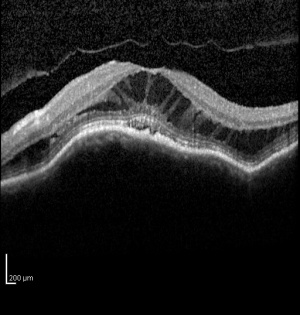

Myopic traction maculopathy (MTM), also known as myopic foveoschisis, is a schisis-like thickening of the retina in eyes with high myopia with posterior staphyloma. The pathologic features may also include lamellar or full-thickness macular holes, shallow foveal detachments, and inner retinal fluid.[1] It has been suggested that the schisis-like thickening represents edema from traction rather than a true schisis.[2]

MTM is estimated to affect between 9 and 34% of highly myopic eyes with posterior staphyloma.[1][3][4]It is more prevelant in populations with high myopia and may be more prevalent in women.[2] In 1958, Phillips described localized posterior retinal detachments in patients with high myopia and posterior staphylomas without the presence of retinal holes.[5] He postulated that myopic chorioretinal atrophy and the presence of a staphyloma were likely involved in the pathogenesis. Prior to optical coherence tomography (OCT), MTM was difficult to distinguish from shallow retinal detachments and macular holes, particularly because slit-lamp biomicroscopy is limited in patients with myopic chorioretinal atrophy.[6][7] Takano and Kishi first reported detection of MTM using OCT in 1999. They described foveal retinal detachment and foveoschisis in patients with high myopia with posterior staphylomas.[4] Since then, spectral-domain OCT has been shown to be even more sensitive in detecting the pathologies associated with MTM.[6]

The diagnosis of MTM was difficult prior to OCT because it was difficult to distinguish from shallow retinal detachments and macular holes using slit-lamp biomicroscopy.[6][7] Spectral domain OCT has been shown to be sensitive in detecting the pathologies associated with MTM.[6] Panozzo et al described a system to categorize OCT findings in MTM. That system originally focused on the presence epiretinal membrane, vitreomacular traction from incomplete vitreomacular separation, retinal thickening with or without cystoid edema, separation of the neurosensory retina into two or more layers, retinal detachment, lamellar or full thickness macular holes.[1]